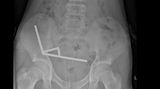

Když Reymy po roce svou zkušenost zveřejnila, nikdo jí prý nechtěl věřit, přestože ukázala i rentgenové snímky. Na svého psa se po incidentu nikdy nezlobila. „Ani na vteřinu ne,“ ujistila.

Chirurgové pak při gastroskopickém zákroku a v lokální anestezii lžíci z těla pacientky vyjmuli. Nesměla přitom polykat, jinak by prý předmět mohl klesnout ještě níž.